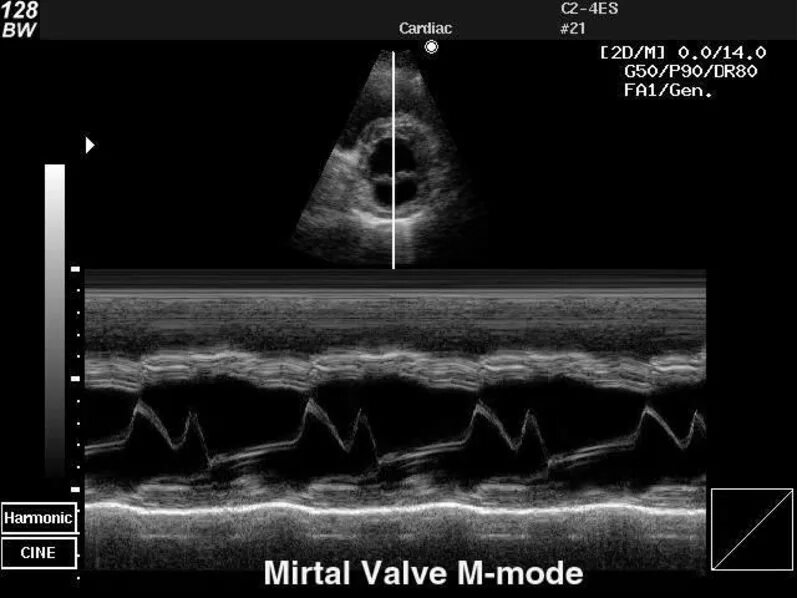

Режимы узи аппарата